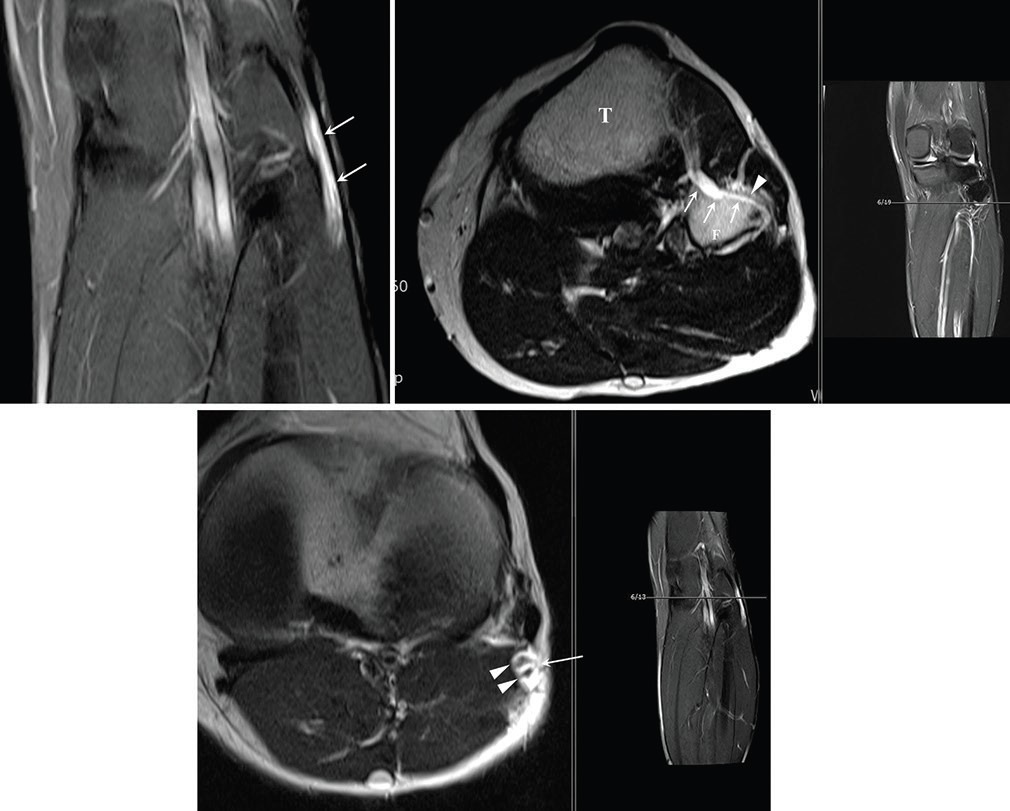

이번 성과는 지난 2018년 국제 학술지 ‘Asian Journal of Neurosurgery’에 발표한 손 교수의 증례 보고인 ‘비골신경 마비를 유발하는 신경곁조직 아래막 결절종’ 에서부터 시작되었다. 당시 손 교수는 2016년 메이요 클리닉 연구팀이 최초 확인하여 학계에 보고한 ‘신경곁조직 아래막(subparaneurial)’ 결절종이라는 매우 희귀한 변이를 실제 임상 현장에서 발견하고, 이를 성공적으로 치료한 과정을 상세히 기술하였다. 이는 기존에 알려진 신경외막(epineurium) 내부의 결절종과는 달리, 신경을 감싸는 더 깊은 층인 신경곁조직 아래 공간을 따라 낭종이 확산되는 독특한 병태생리를 규명한 중요한 전환점이 되었다.

이후 손 교수는 지난 8년간 비골신경, 척골신경, 요천추신경총, 궁둥신경 등 인체 전반의 말초신경에서 발생하는 증례들을 지속적으로 추적하며 임상 데이터를 축적해 왔다. 2025년 메이요 클리닉과의 공동 연구 과정에서 이러한 데이터는 연구의 완성도를 높이는데 기여한 것으로 알려졌다. 연구팀은 신경곁조직 아래막 결절종이 신경의 주 경로뿐만 아니라 해부학적으로 분리된 여러 신경 분지로까지 확산될 수 있다는 병태생리 파트 1, 2 논문을 완성하였다. 이는 활액이 이동하는 미세한 해부학적 통로를 완벽히 이해해야만 재발 없는 치료가 가능하다는 사실을 과학적으로 입증한 것이다.